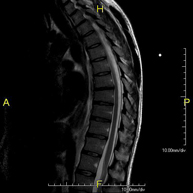

- Thoracic spine MRI

This non-invasive diagnostic procedure uses an electromagnetic field and radio waves (from a transmitter and receiver) to acquire high-definition anatomical images of the thoracic spine. It is a radiation-free procedure. Indicated for: trauma, degenerative problems, hernias, tumours.

- Thoracic + lumbar spine MRI

This non-invasive diagnostic procedure uses an electromagnetic field and radio waves (from a transmitter and receiver) to acquire high-definition anatomical images of the thoracic and lumbar spine. It is a radiation-free procedure. Indicated for: trauma, spinal degeneration, hernias.